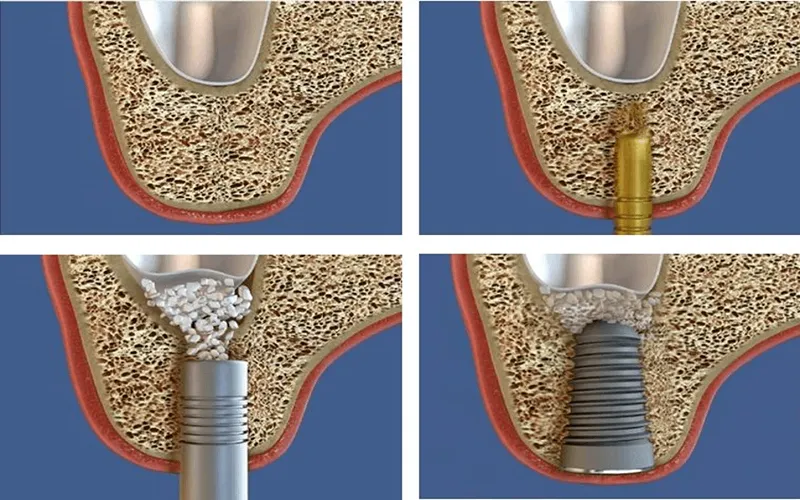

امروز دندانپزشکان به صورت گسترده از روش سینوس لیفت باز استفاده می کنند. به منظور انجام جراحی سینوس لیفت باز به استخوان با اندازه 5 سانتی متر احتیاج دارید. در روش سینوس لیفت باز، برش روی باف لثه ایجاد شده و بعد سینوس به بالا حرکت داده می شود.

پس از طی کردن این مرحله، قسمت خالی از طریق مواد پیوندی و پودر استخوان کامل و پر می شود. جراح باید به منظور انجام عمل سینوس لیفت باز تبحر زیادی داشته باشد. پس جهت انجام این عمل جراحی به هر مرکز دندانپزشکی مراجعه نکنید.

| 1 | قسمتی از لثه در بخش جانبی فک بالا بریده شده و روی استخوان سوراخی ایجاد می شود |

| 2 | سپس، از طریق این سوراخ، دندانپزشک مخاطی را پیدا می کند که سینوس داخل آن را می پوشاند |

به این غشاء، اشنایدر هم می گویند.

سپس

| 3 | دندانپزشک می تواند با ابزارهای مخصوص جراحی و با رعایت احتیاط بدون آسیب به غشاء، مخاط سینوس را بلند کرده و مواد استخوانی را در آنجا می ریزد |

| 4 | بعد از اینکه عمل لیفت سینوس باز تمام شد، زخم ها بخیه زده می شوند |

جراحی سینوس لیفت برای ایمپلنت به صورت بسته با هدف بالا بردن سینوس ماگزیلاری و پر کردن شکاف با مواد لازم پیوند استخوان انجام می شود. این پروسه به تشکیل بافت استخوانی کمک زیادی می کند.